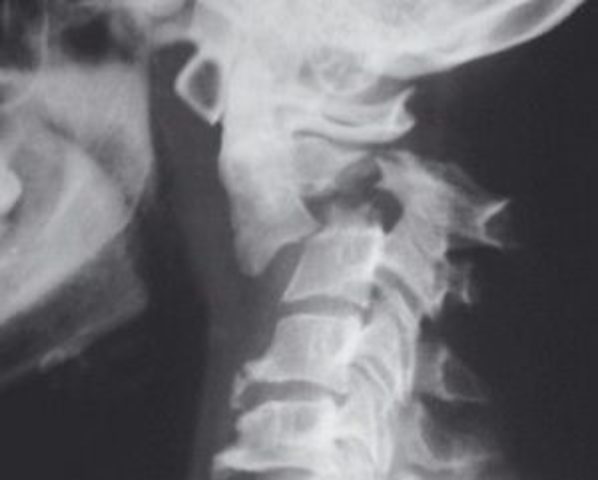

Columna cervical

Después de muchos, muchos estudios el Dr. Cloward diseño los instrumentos que le permitieron desarrollar la técnica quirúrgica para reemplazar el cuerpo vertebral fracturado

Cada vez que operaba encontraba que podía mejorar la técnica quirúrgica y por esta razón su técnica fue empleada para el tratamiento del trauma cervical anterior, por muchos cirujanos

Sin embargo la forma del injerto oseo del dr. Cloward no era el mas adecuado y fue cuando los neurocirujanos Smith y Robinson y sus colaboradores se arriesgaron a modificarlo

Llegando a la conclusión que este debía parecerse anatómicamente al cuerpo vertebral por eso se ese cambia su forma y se decide extraerlo de la cresta iliaca.

No obstante que fue una gran idea, los resultados no eran los mejores entonces aparece en el panorama medico el Dr caspar, y se arriesga a crear un sistema de pacas y tornillos para fijar el colgajo